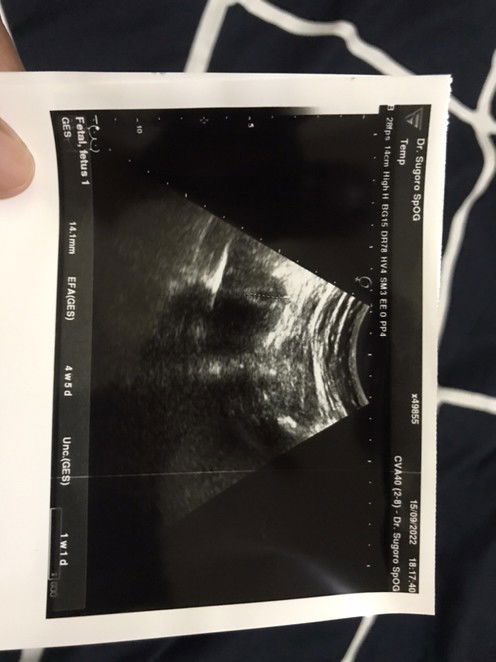

Hai Moms, mau tanya, moms pada USG di minggu ke berapa aja? dan rata-rata janin dan detak jantung janin sudah ada di minggu ke berapa moms? Kalau saya USG pertama di usia 4w5d, kedua 7w2d, dan akan USG lagi nanti di usia 10w, kira kira sudah ada janin belum ya 🙏🏽 #ingintahu #firstmom #firstbaby